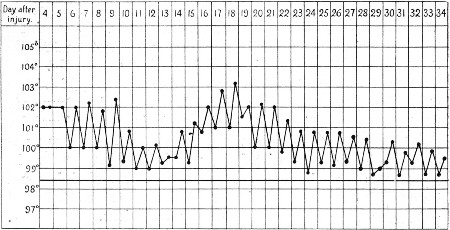

2. Case of Hæmothorax with Recurrent Hæmorrhages 395

3. Primary and Secondary Rises of Temperature in Hæmothorax, Recovering Spontaneously 402

4. Secondary Rise of Temperature in Hæmothorax 403

5. Falls of Temperature in Hæmothorax following Paracentesis 404

6. Secondary Hæmothorax, Spontaneous Fall of Temperature 405